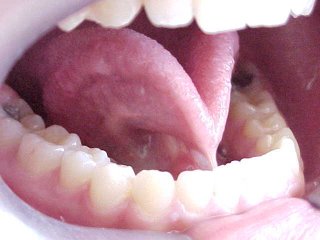

Tratamento cirúrgico da "Língua Presa". Frenectomia ou Frenulotomia Lingual

| Esta técnica cirúrgica destina-se à liberação dos movimentos funcionais da língua . Neste caso a inserção mais anterior se mostra aderida à gengiva: